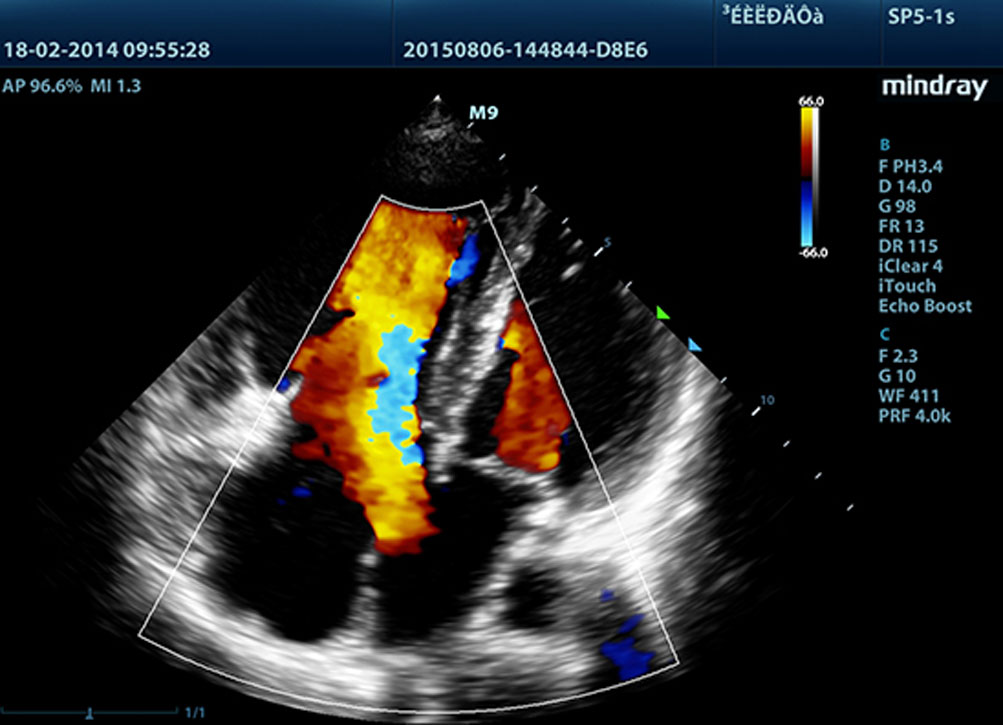

Fornendo immagini pi├╣ nitide, tutte le sonde compatibili con M9 sono dotate della tecnologia Mindray tecnologia trasduttore 3T, unica nel suo genere. Migliorato con l'aggiunta della tecnologia monocristallo, M9 offre una migliore penetrazione e un flusso dinamico del colore, in particolare durante la scansione di pazienti difficili.

THI (Tissue Harmonic Imaging)

Utilizzando le seconde armoniche generate dagli strati limite dei tessuti, il THI migliora in modo significativo la risoluzione del contrasto e migliora la qualit├Ā delle immagini soprattutto per i soggetti tecnicamente difficili.

TSI (Tissue Specific Imaging)

Il TSI (Tissue Specific Imaging) ottimizza la qualit├Ā dell'immagine in base alle propriet├Ā del tessuto in corso di scansione. Sono disponibili quattro opzioni di imaging tra cui in generale, muscolo, fluidi e grassi.